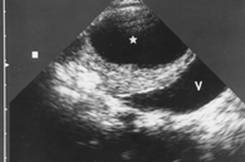

Valva uretrala posterioara-incidenta transversala arata o VU cu tabeculatie si pereti extrem de ingrosati